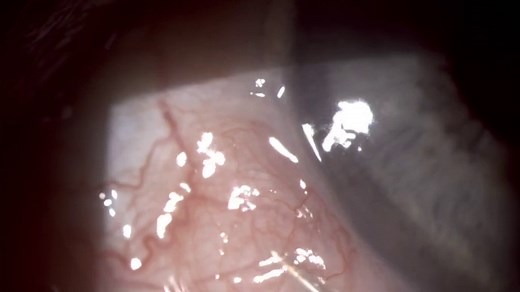

Eye Cyst Removal - Conjunctival Inclusion Cyst

38.2K views

Mar 20, 2019

YouTube

YouTube's Greatest Medical